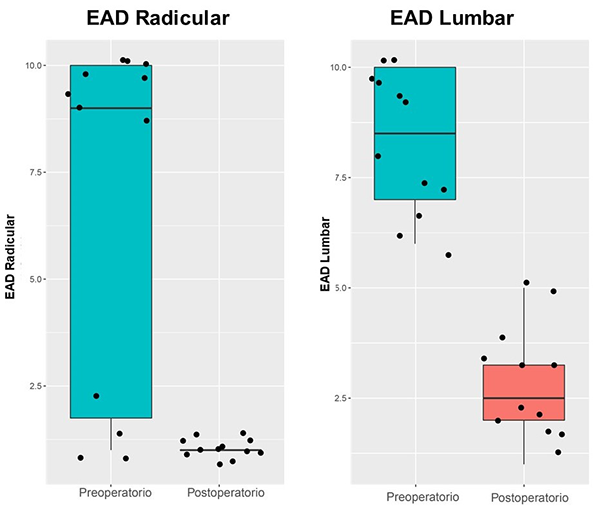

No se registraron subsidencias en las radiografías de control del postoperatorio inmediato ni a los 6 meses. Ningún caso necesitó descompresión por vía posterior complementaria. Los niveles instrumentados incluyeron un segmento espinal único en todos los casos, excepto uno en el cual se instrumentaron 2 discos. El nivel L4-5 fue el más abordado incluyendo 7 pacientes (58%), seguido del espacio L3-4 con 4 pacientes (33%) y el espacio L2-3 con 2 pacientes (16%). El tiempo operatorio promedio fue de 121,2 minutos. El sangrado intraoperatorio tuvo un promedio de 93 ml (rango de 80 a 120 mL). Todos los pacientes se movilizaron en el primer día postoperatorio sin inconvenientes. El resultado clínico fue satisfactorio, mostrando métricas favorables tanto en términos de dolor lumbar como radicular a los 6 meses de seguimiento (Gráfico 1).

Gráfico 1: Box-plot demostrando la diferencia entre dolor radicular y lumbar pre y postoperatorio. En ambos casos, la diferencia fue significativa, con una clara disminución del dolor.